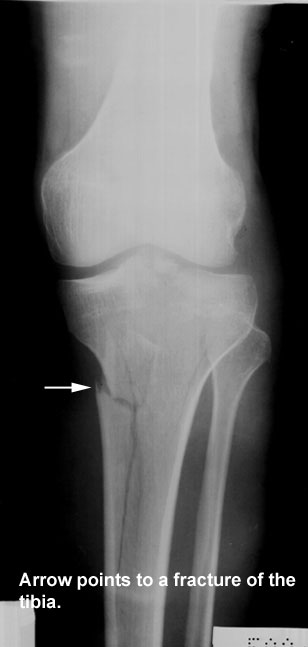

A 24-year-old football player was taken to the emergency room after receiving a blow to the left leg that resulted in severe pain and inability to stand up. The attending physician was able to locate a very painful area just below the knee and suspected a fracture to the fibula. He ordered a plain AP and lateral x-ray of the leg and knee. A clear spiral fracture in the left fibular neck and a cracked tibial shaft were shown on the x-ray. The patient was given analgesics, and a thorough neurological examination was done. No signs of nerve injury were detected. A plaster cast was applied, and the patient was discharged.